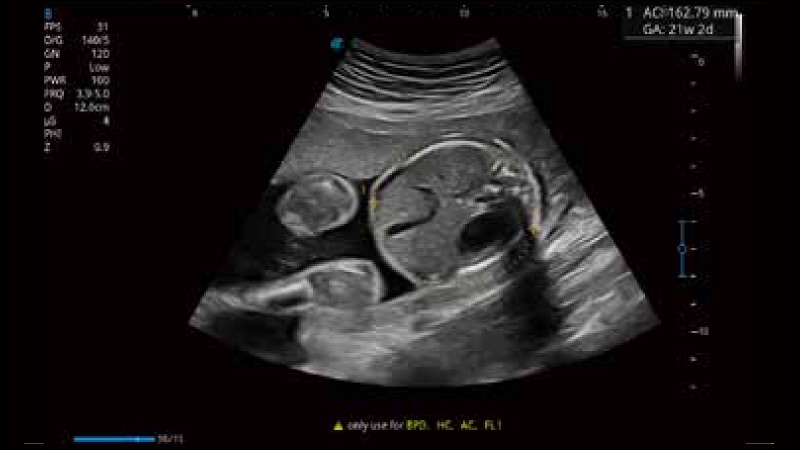

開立醫(yī)療通過不斷的技術(shù)創(chuàng)新,為大眾的生命健康提供持續(xù)關(guān)愛。P12 Plus采用全新一代超聲成像平臺(tái),新平臺(tái)旨在將真實(shí)還原組織解剖結(jié)構(gòu)作為首要目標(biāo)。平臺(tái)采用全新集成化硬件模塊,搭載新一代芯片,系統(tǒng)性能得到大幅提升,為您的診斷提供了豐富的臨床信息。優(yōu)異的圖像表現(xiàn),豐富的探頭配置,全面的應(yīng)用功能,為您日常診斷提供了可靠的助手。